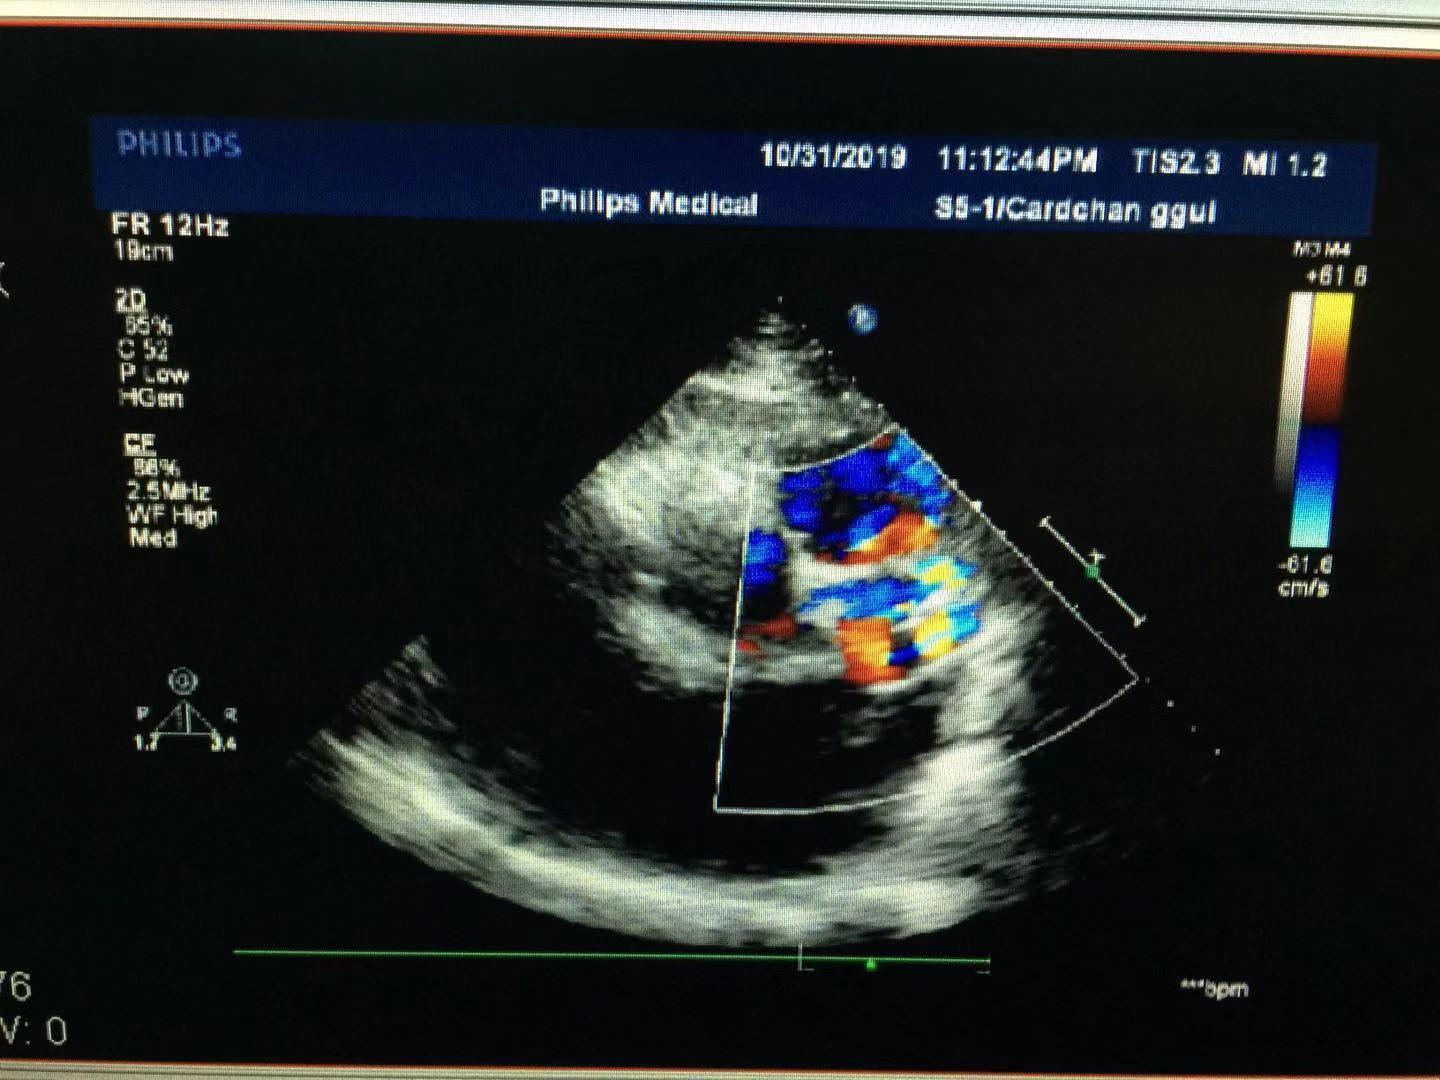

(迂曲扩张的左冠状动脉)

超声所见:全心大,肺动脉主干内径增宽。左冠状动脉迂曲增宽,可视长度明显增加,开口处内径约14mm,增宽的左冠状动脉沿左房越过房间隔开口于右心房,瘘口直径约8mm。房、室间隔连续完整,左室侧后壁运动减弱,余室壁运动尚可。各瓣膜形态正常,二尖瓣、三尖瓣、主动脉瓣开启可,关闭欠佳。心包腔内探及液性暗区,左室后壁深约17mm,右室之前深约13mm。CDFI:于右房内可见以舒张期异常血流信号。二尖瓣、三尖瓣口可见收缩期返流信号。主动脉瓣口可见舒张期返流信号。